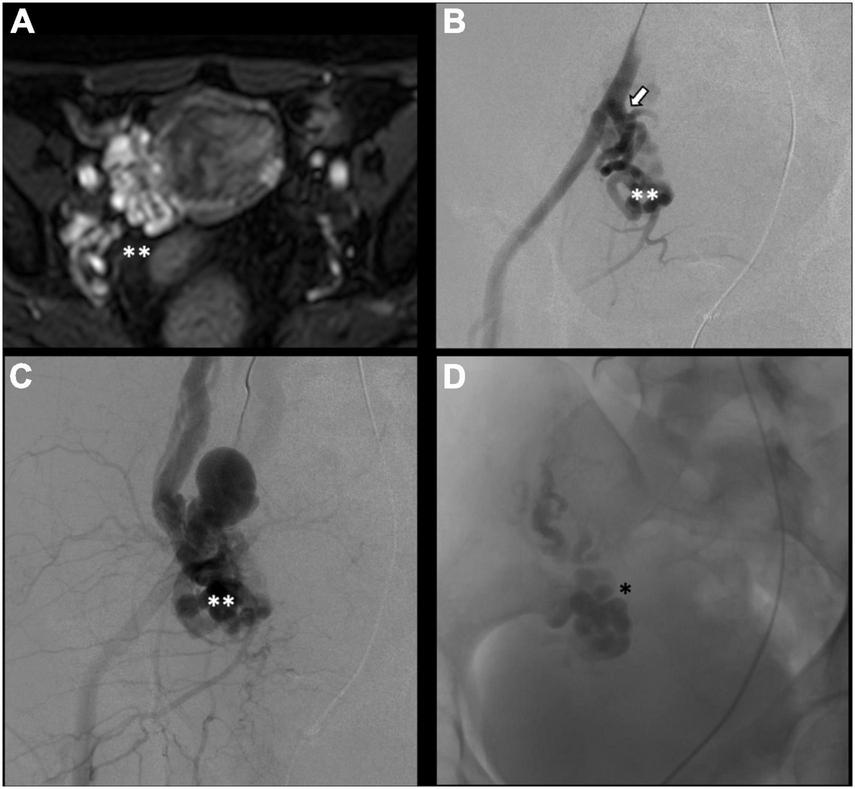

There is no consensus on how to report results, and the final results are very heterogeneous. Though, few studies, systematic reviews, and randomized trials have displayed no remarkable differences between embolization materials in terms of outcome (16, 79, 86). Furthermore, studies have reported an overall rate of complete, excellent, or moderate improvement of 75% at 4–8 weeks and more than 80% at an average of 45 months post-procedure, regardless of the technique or agent used (16, 87–90). Figure 2 shows an example of type Ia pelvic varices and subsequent vaso-occlusive therapy by means of multiple endovenous coils. Endovascular vaso-occlusive therapy is also applicable in the nutcracker phenomenon, with reported improvement in 56 to 98% of patients (17). Figure 3 shows an example of nutcracker phenomenon corresponding to a IIb pelvic varix stage. In the case of arteriovenous fistula (type IV pelvic varices), distal embolic efficacy can be achieved with liquid agents, as shown in Figure 4.

FIGURE 3

Type IIb pelvic varices in a 54 yo female due to nutcracker syndrome. (A,B) Computed tomography (CT) phlebography shows the left renal vein (open arrow) compressed by the mesenteric artery (white arrow) and aorta (black arrow). (C,D) Conventional phlebography shows dilated left ovarian vein (single white asterisk) with left-sided pelvic varices (double white asterisks), treated with multiple plugs (single black asterisk) and coils (double black asterisks).